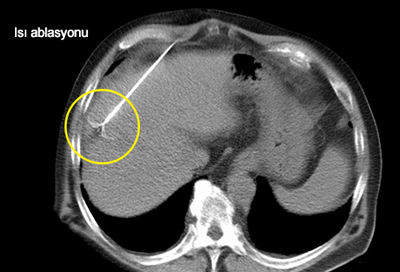

Ablasyon

Kanserli dokuyu değişik yöntemlerle öldürme tekniğidir:

• Yakma: Mikrodalga veya radyofrekans (RF) kullanılarak tümör hücreleri yakılabilir